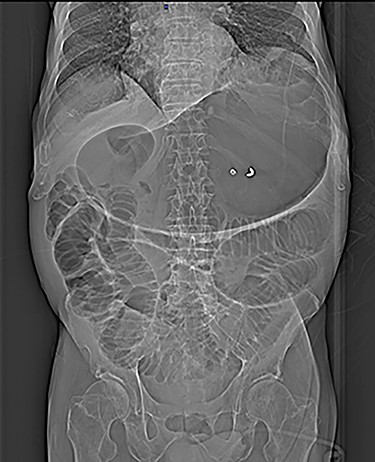

Plain abdomen radiography was performed at the ED and showed distended stomach and small bowel with air-fluid levels (Fig. 1). No free gas in the peritoneal cavity was seen. A contrast-enhanced CT scan revealed a huge gastrectasia with liquids, small bowel distention due to a suspected adherent bridle. Some loops of the ileum showed emphysematous walls (Fig. 2). A minimal perihepatic liquid effusion was observed due to suffering bowel.

Axial CT scans of abdomen show gastrectasia with the NG tube just inserted (A) and a suspected image of bowel emphysematous walls (B).